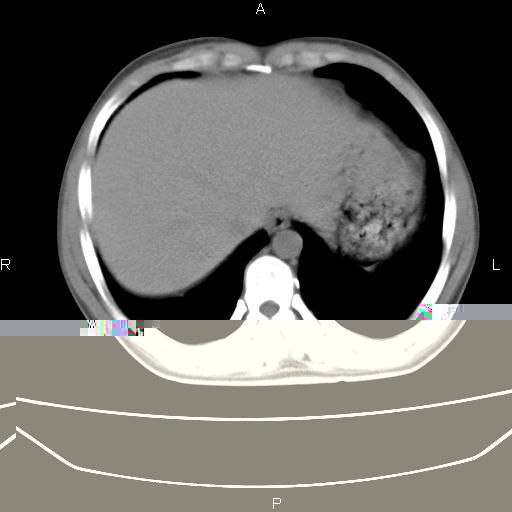

患者,男,40岁。间断发热,咳嗽二十余日。体温最高达38.9° 在当地诊所抗炎治疗三天后体温降至正常,患者自行停药。今又发热。胸片示,左下肺阴影。

左下肺片状高密度影,境界模糊,密度不均,考虑感染性病变可能性大,建议抗炎治疗后复查。左肺门增大,不除外占位性病变,必要时支气管镜检。

建议强化或纤支镜观察,考虑肿瘤性病变可能性大